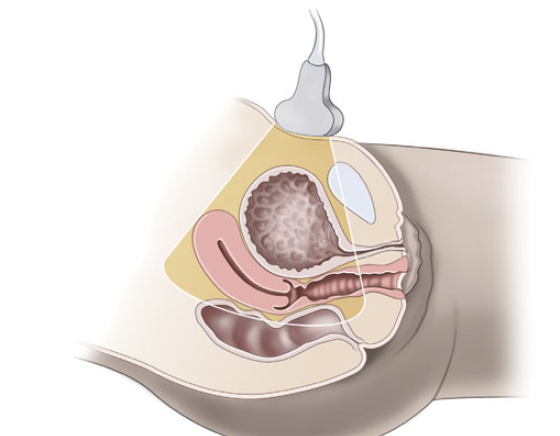

Technique for transabdominal pelvic ultrasound [6-7]

Patient positioning: Place patient in supine position with knees flexed if possible

Probe Selection: Low frequency curvilinear probe works best as this provides the depth needed to assess the uterus and areas deep to the GU tract.

Technique: Expose lower abdomen and pelvic area.  Obtain a midline sagittal view and fan the probe left and right to assess the lateral aspects of the pelvis. Attempt to include the ovaries if possible. Then rotate the probe 90 degrees to obtain a transverse view, and fan the probe superiorly and inferiorly to image the entire pelvis.  For both views, ensure there is adequate depth to see behind the bladder and uterus to assess for free fluid.

Pelvic anatomy & probe placement [7]]